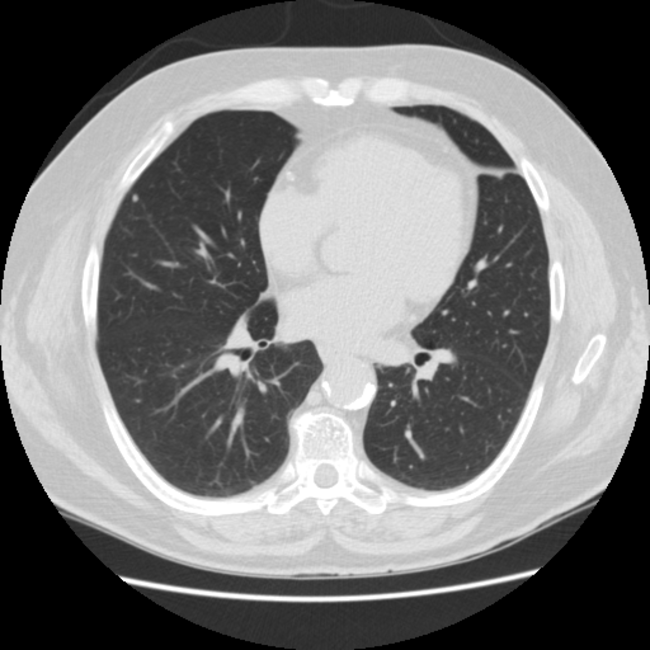

【EIRL Chest CTによる表示例】

1. 標準線量CT